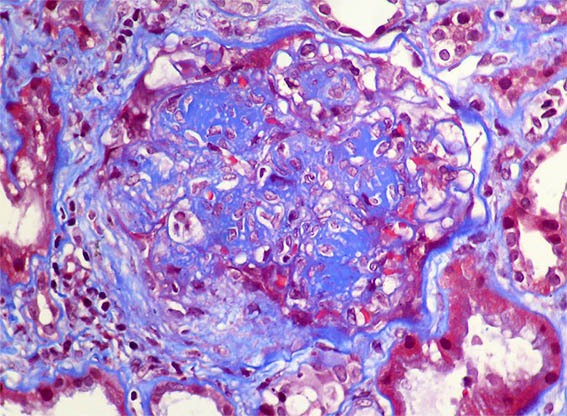

Figura 4. Tricrómico de Masson, X400.